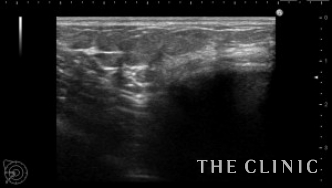

エコー所見です。

右のバッグの周囲のカプセルは肥厚して石灰化が疑われます。

わずかですが、バッグの周囲にシリコンが漏れています。